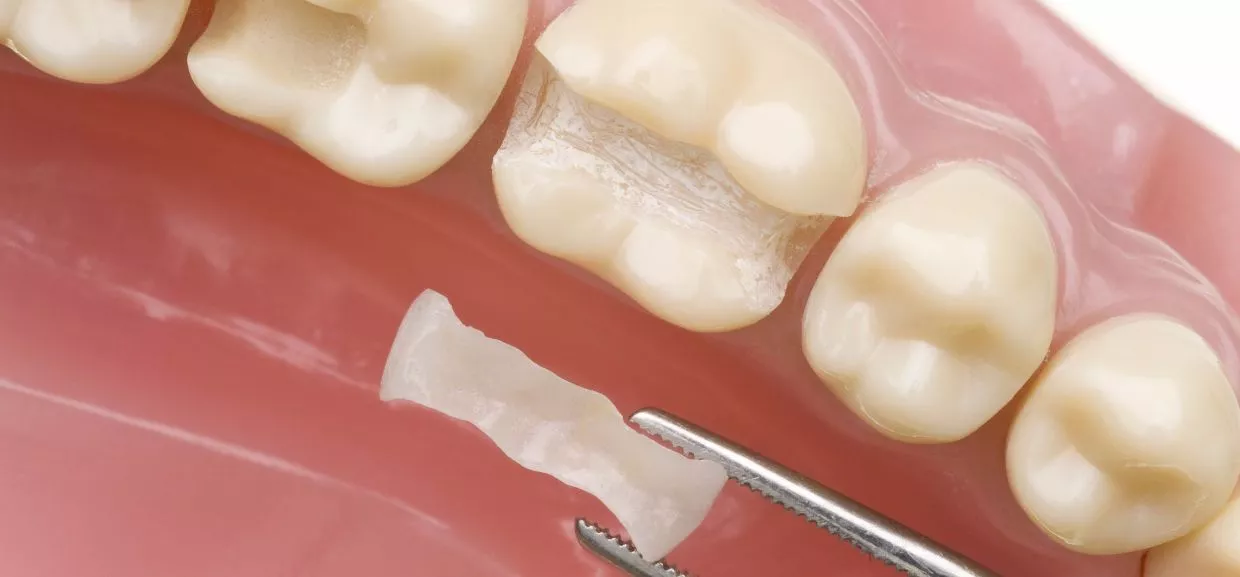

Moderne Alternativen: Kompositfüllung & Kompositinlay

Die Kompositfüllung (auch als Kunststofffüllung bekannt) wird direkt im Zahn verarbeitet – in nur einer Sitzung. Sie ist preisgünstig, zahnfarben und hält bei guter Mundhygiene 8 bis 15 Jahre. Komplexere Defekte lassen sich mit einem Kompositinlay versorgen. Dieses wird ausserhalb des Mundes gefertigt und in den Zahn geklebt – präzise, ästhetisch und besonders haltbar. Kompositinlays sind weniger rissanfällig, jedoch aufwendiger und benötigen zwei Sitzungen.

Moderne Kompositfüllung als ästhetische Alternative zu Amalgam – biokompatibler Füllungsersatz in der ACC Zahnklinik Basel

AMALGAM & FÜLLUNGSERSATZ

Porzellaninlays – die Premiumlösung

Ein Porzellaninlay bietet höchste Ästhetik und Präzision. Es wird durch einen Zahntechniker gefertigt und wie das Kompositinlay mit Kompositkleber eingesetzt. Die Haltbarkeit liegt bei 10 bis 15 Jahren. Porzellan ist besonders abriebfest und eignet sich auch für schwierige Zahnsituationen. Nachteile sind die höheren Kosten, die Rissanfälligkeit und der Aufwand (grössere Zahnkavität, zwei Termine).